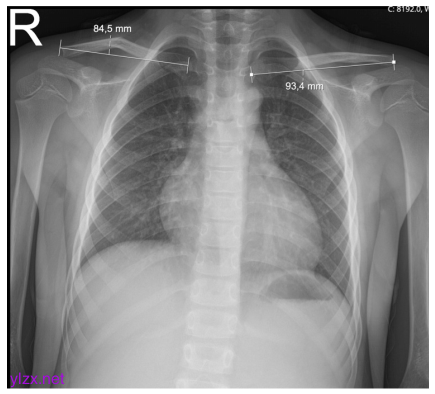

锁骨缩短测量示例。缩短量是通过从对侧未受伤锁骨的长度中减去骨折锁骨的长度(93.4-84.5=8.9 mm)来测量的。缩短百分比是通过将缩短量除以对侧未受伤锁骨的长度来确定的(8.9/93.4 x 100=9.53%)。